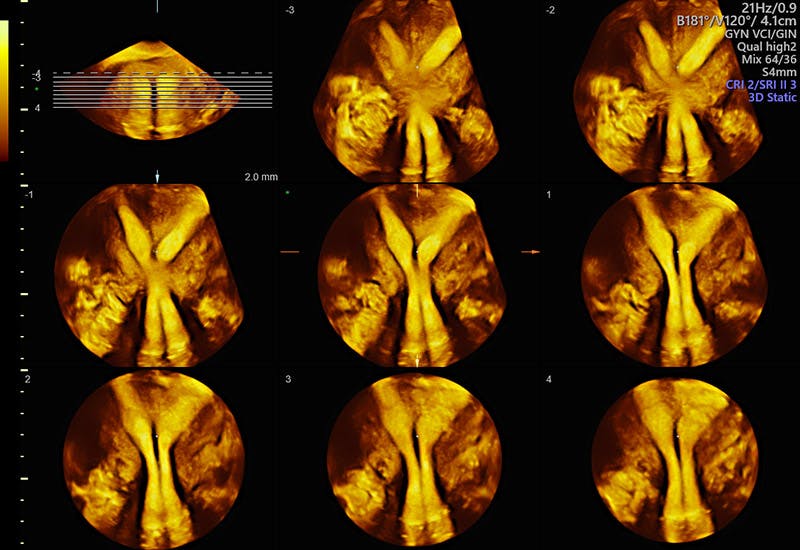

Uterine anomalies such as this Septate Uterus are readily seen with Voluson 3D ultrasound.

Voluson 3D tools such as OmniView help detect uterine shape anomalies that can impact conception.